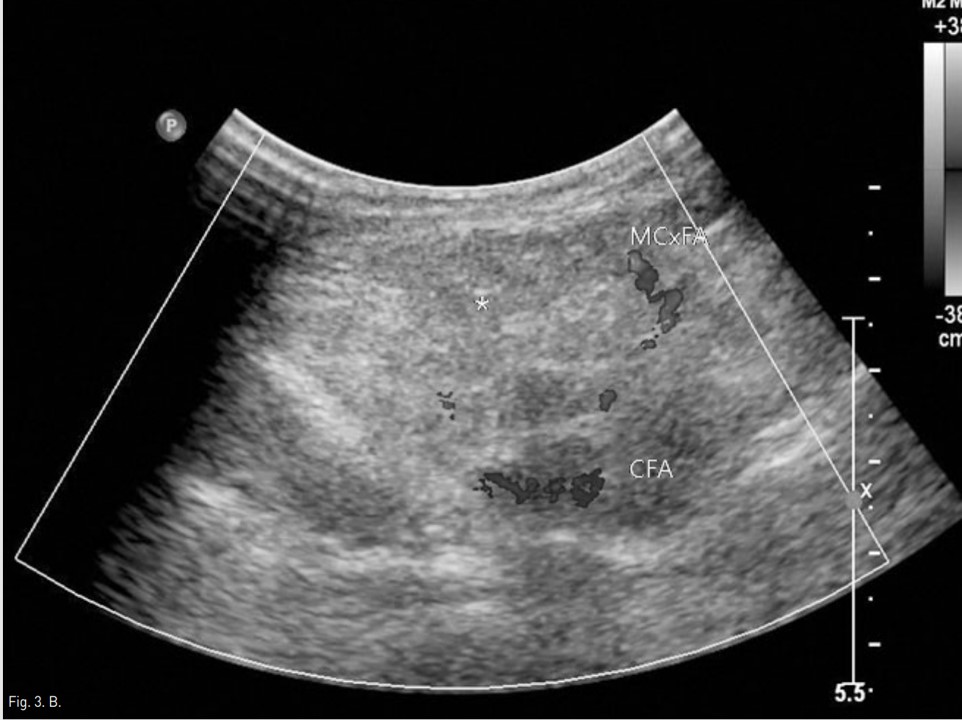

Fig. 3. B

Fig. 3A, B. 3D volume rendering with left anterior oblique projection image (A) obtained 12 days after procedure shows glue complex (arrow) in the pseudoaneurysm with no residual filling of contrast media. Also, color doppler US (B) obtained the same day shows complete obliteration of pseudoaneurysm(asterisk) with the patent common femoral and medial circumflex femoral arteries.